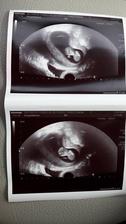

Náš zázrak 2017

Zázrak se snad stane skutečností...